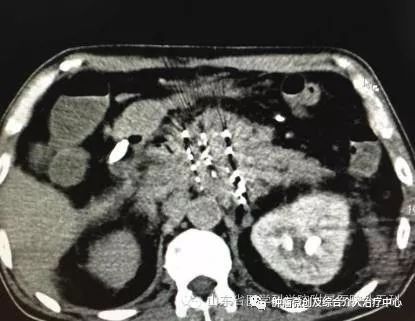

8、CT/B超引导下肿瘤射频消融及碘125粒子植入介入治疗。